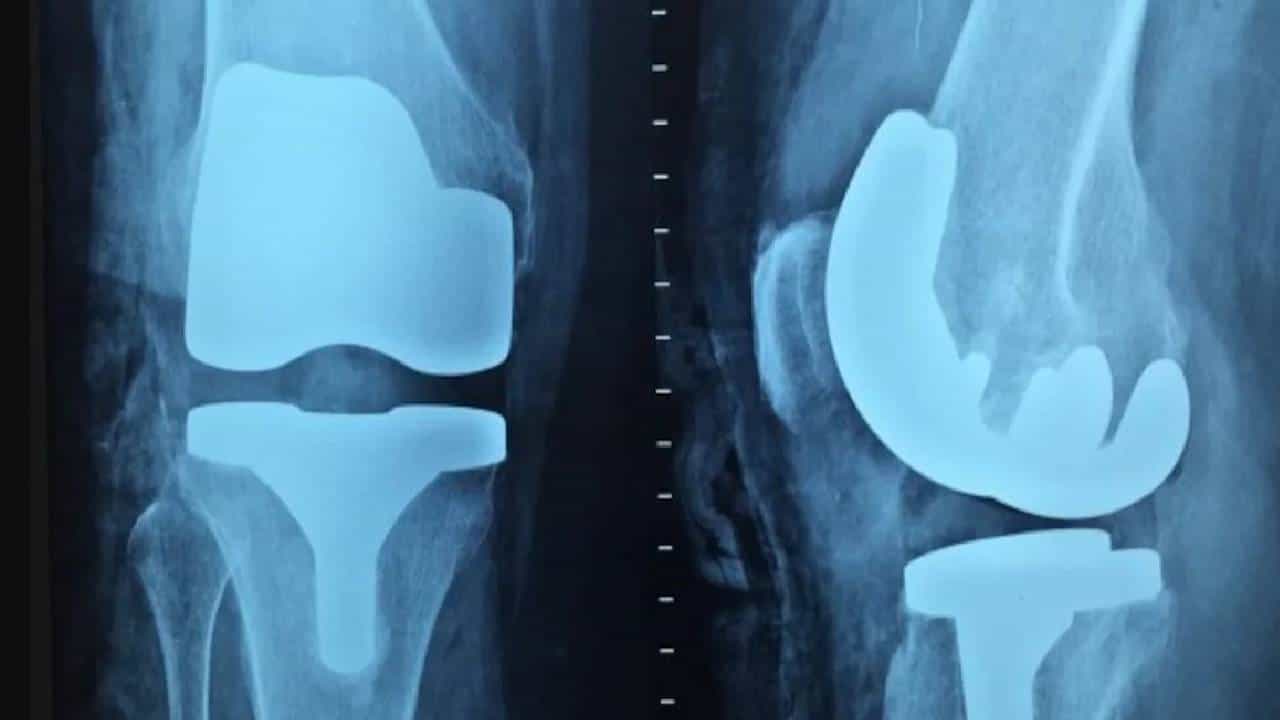

World Bone And Joint Day: वल्ड बोन ॲण्ड ज्वाईंट डे निमित्त आज आपण बघणार आहोत. आपल्या घरातील वयोवृद्धांच्या हाडाची निगा (Bone care in the elderly) कशी राखावी ते, कारण वयोवृद्धांना वाढत्या वयासह डोळ्यांच्या किंवा संतुलनाशी संबंधित (Relating to balance) समस्या जाणवतात, ज्यामुळे त्यांचे पडण्याचा धोके वाढतात. ओल्या आणि निसरड्या पृष्ठभागावर हा धोका अधिक असतो. ज्यात ऑस्टिओपोरोसिस आणि संधिवाताचा समावेश असून या मुळे हाडे वाढत्या वयानुसार कमकुवत होऊ लागतात. ऑर्थोपेडिक सर्जन सांगतात की, “ऑस्टिओपोरोसिसमुळे, अगदी किरकोळ पडल्यानेही फ्रॅक्चर होऊ शकते, सामान्यतः मनगट, मणक्याचे आणि नितंबाच्या हाडांमध्ये फ्रॅक्चर (Fractures in bones) होतात. डोके आणि छातीला गंभीर दुखापत देखील होऊ शकते. ऑस्टियोपोरोटिक हाडांच्या फ्रॅक्चरला बरे होण्यास वेळ लागतो आणि दीर्घकाळ विश्रांतीची आवश्यकता असू शकते. ऑस्टियोपोरोटिक हाडांची शस्त्रक्रिया देखील आव्हानात्मक असते. त्यामुळे, पडणे टाळण्यासाठी, विशेषतः वयानुसार, अडचणी टाळण्यासाठी या सर्व काळजी घेणे आवश्यक आहे.”

तज्ज्ञ सांगतात, की “वृद्ध लोकांना पावसाळ्यात दुखापत होण्याचा धोका जास्त असतो. घरात किंवा कामाच्या ठिकाणी ओलसर फ्लेाअर(फरशी) किंवा ओबड-धोबड रस्त्यांवर तोल गेल्यामुळे अपघात होवून पडण्याच्या अधिक भीती असते. ज्येष्ठ नागरिकांमध्ये ऑस्टिओपोरोसिस ६० वर्षांपेक्षा जास्त वयाच्या बहुतेक रुग्णांमध्ये आढळतो. विशेष म्हणजे पुरुषांपेक्षा स्त्रियांमध्ये जास्त प्रमाण आहे. हिप, मणक्याचे, मनगटाचे, घोट्याचे किंवा खांद्याचे फ्रॅक्चर आदी दुखापती सामान्य आहे.